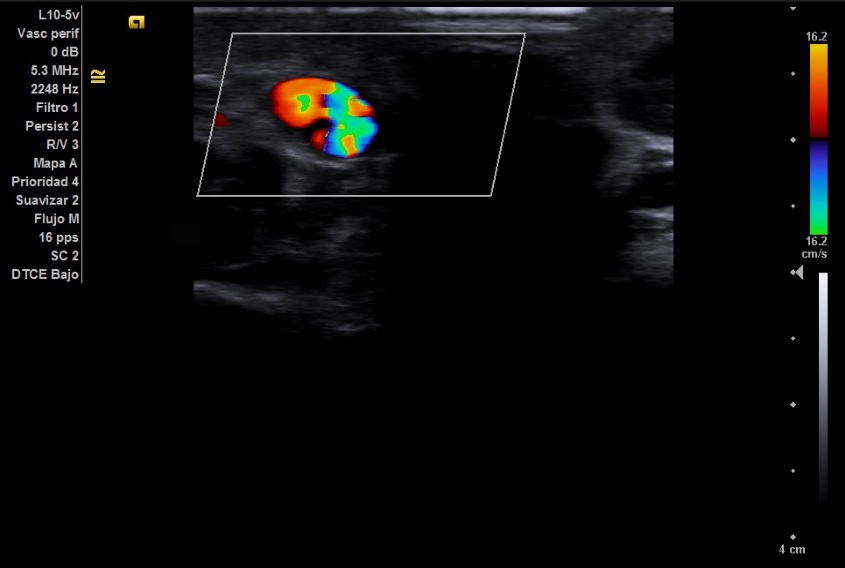

Imagen 3 y 4: Corte transversal. Signo del Yin Yang.

Secuencia doppler en la que podemos ver dos flujos en el interior de la lesión, dando lugar al conocido como signo del Yin Yang.